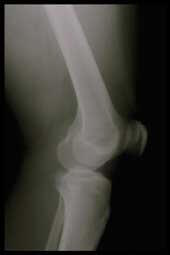

| Arthrite et polyarthrite Rhumatoïde

Dans l'arthrite comme dans la polyarthrite rhumatoïde, la destruction du cartilage et de l'os semble principalement due à l'action d'une matrice d'enzymes (les métalloprotéinases) |

L'inflammation est la réponse de tissus vivants à une agression mécanique, chimique ou immunologique. Elle est caractérisée par des niveaux élevés de métabolites de l'acide arachidonique qui sont produits le long de deux voies enzymatiques différentes : la cyclo-oxygénase et la lipoxygénase conduisant aux prostaglandines PGE-2 et aux leucotriènes LTB4, des métabolites de premier plan et d'importants médiateurs de l'inflammation. Ils jouent un rôle crucial dans l'arthrite en causant la résorption de l'os, en stimulant la sécrétion de la collagénase et en inhibant la formation des protéoglycanes. |